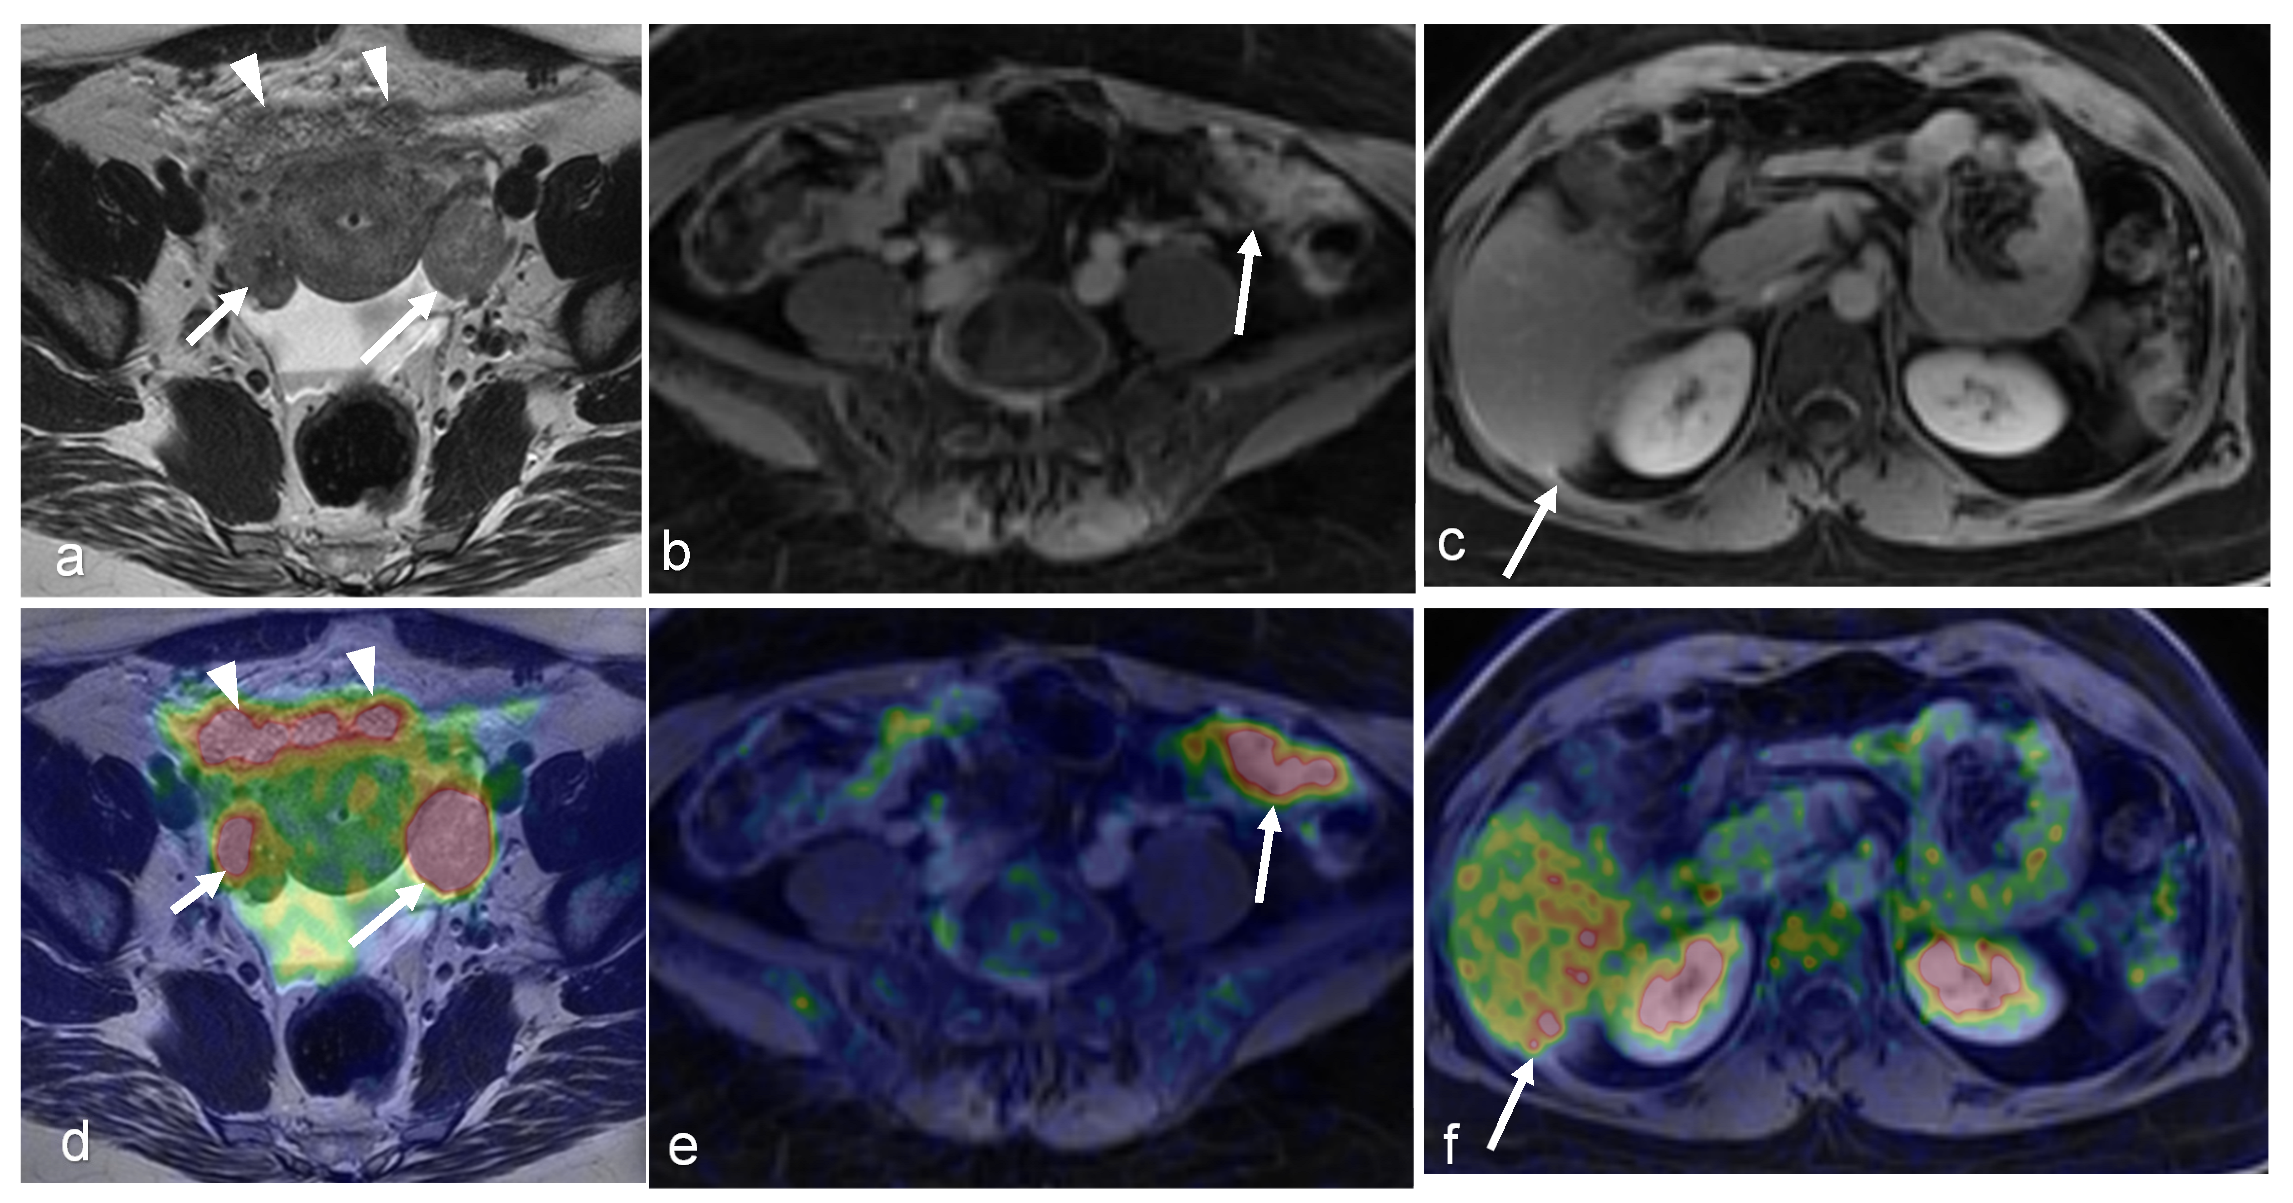

- Chow, L.; Tsui, B.Q.; Bahrami, S.; Masamed, R.; Memarzadeh, S.; Raman, S.S.; Patel, M.K. Gynecologic tumor board: A radiologist’s guide to vulvar and vaginal malignancies. Abdom. Radiol. 2021, 46, 5669–5686. [Google Scholar] [CrossRef] [PubMed]

- Cohn, D.E.; Dehdashti, F.; Gibb, R.K.; Mutch, D.G.; Rader, J.S.; Siegel, B.A.; Herzog, T.J. Prospective evaluation of positron emission tomography for the detection of groin node metastases from vulvar cancer. Gynecol. Oncol. 2002, 85, 179–184. [Google Scholar] [CrossRef]

- Rufini, V.; Garganese, G.; Ieria, F.P.; Pasciuto, T.; Fragomeni, S.M.; Gui, B.; Florit, A.; Inzani, F.; Zannoni, G.F.; Scambia, G.; et al. Diagnostic performance of preoperative [18F]FDG-PET/CT for lymph node staging in vulvar cancer: A large single-centre study. Eur. J. Nucl. Med. Mol. Imaging 2021, 48, 3303–3314. [Google Scholar] [CrossRef] [PubMed]